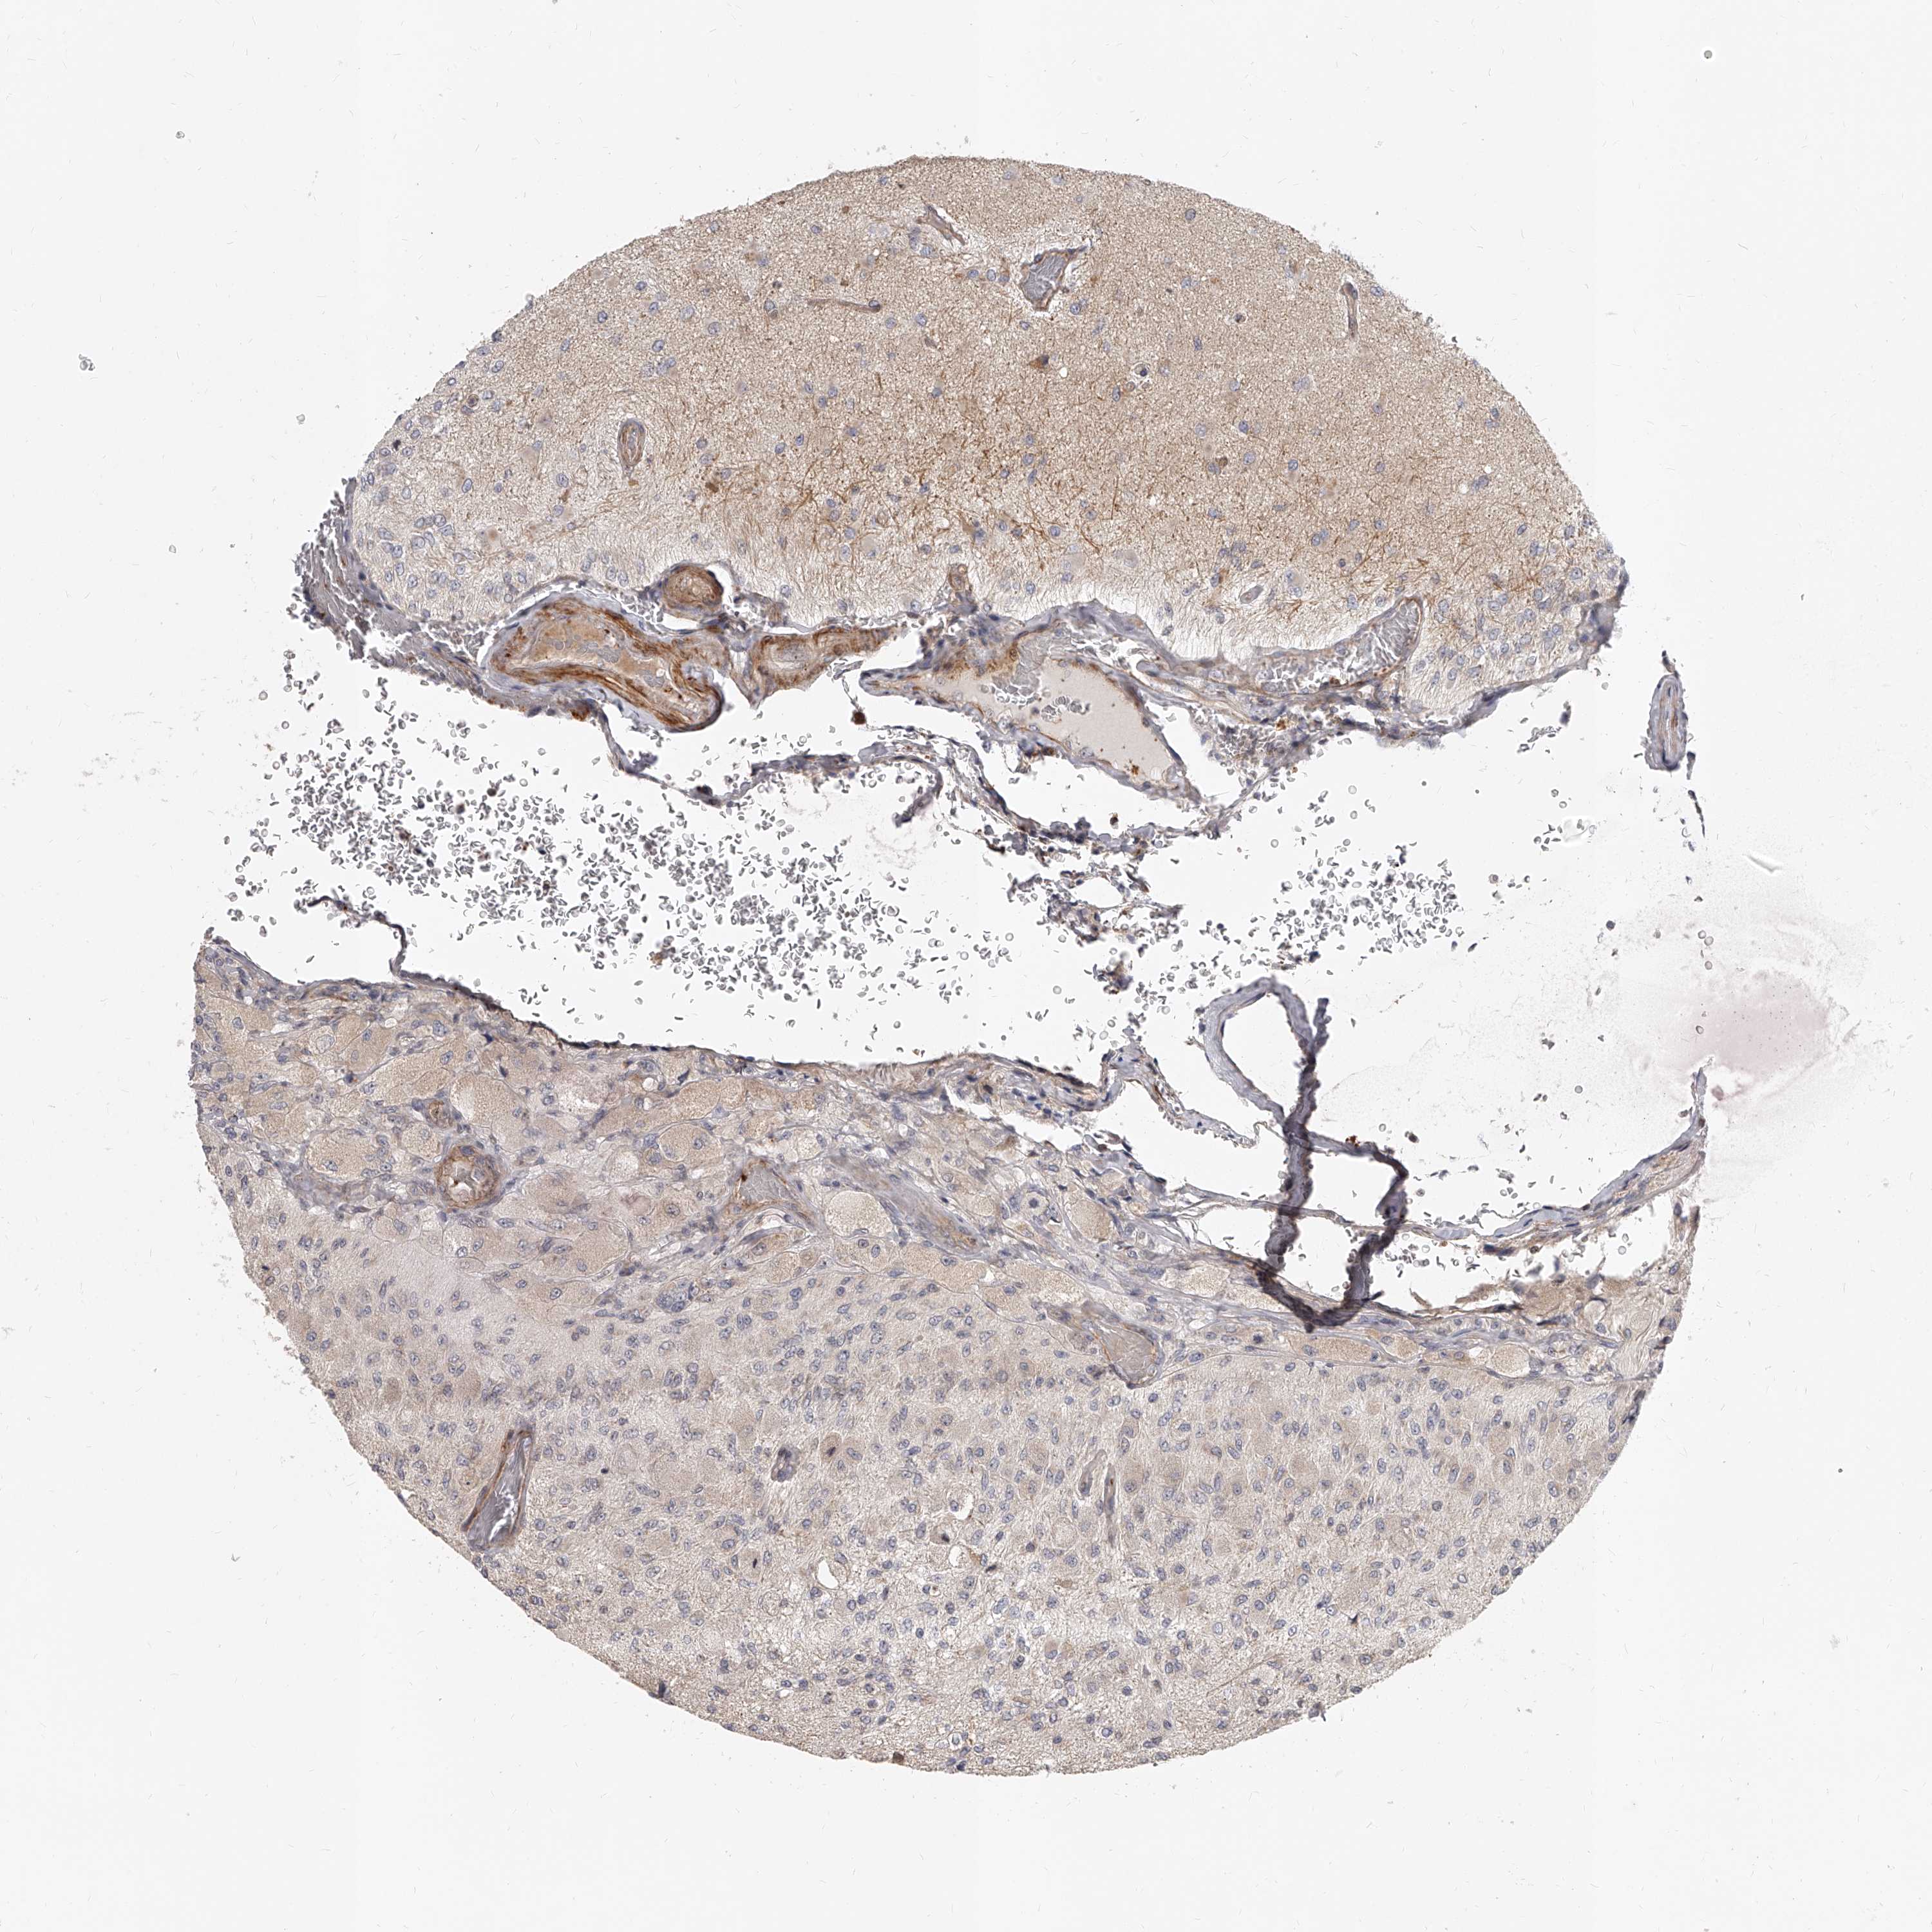

GLIOMA - Protein expressioni

A mouse-over function shows sample information and annotation data. Click on an image to view it in a full screen mode. Samples can be filtered based on level of antibody staining by selecting one or several of the following categories: high, medium, low and not detected. The assay and annotation is described here.

Note that samples used for immunohistochemistry by the Human Protein Atlas do not correspond to samples in the TCGA dataset.

Antibody stainingi

Antibody staining in the annotated cell types in the current human tissue is reported as not detected, low, medium, or high, based on conventional immunohistochemistry profiling in selected tissues. This score is based on the combination of the staining intensity and fraction of stained cells.

Each image is clickable and will lead to virtual microscopy that enables deeper exploration of all samples and also displays staining intensity scores, fraction scores and subcellular localization as well as patient and tissue information for each sample.

Antibody HPA030418

Antibody CAB034154

Glioma, malignant, High grade

Glioma, malignant, Low grade

Glioblastoma, NOS